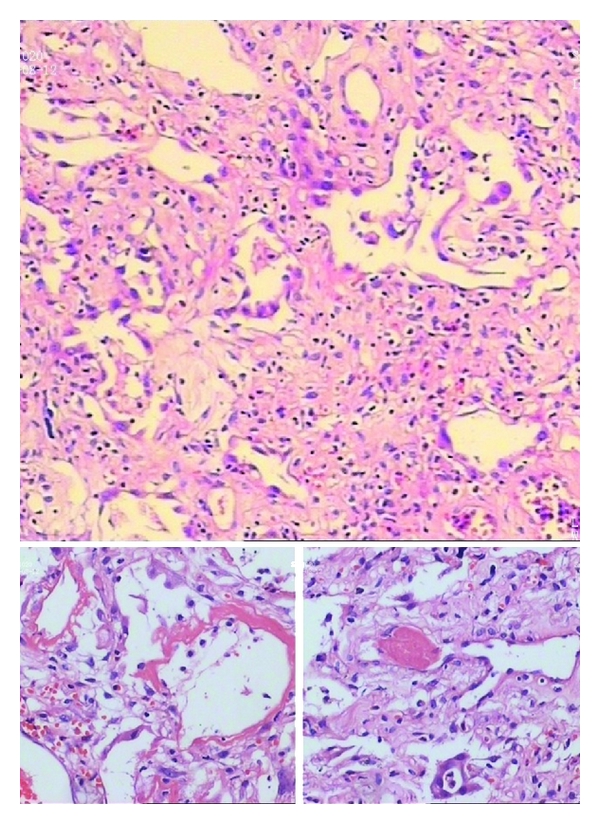

The patient was treated with high-concentration oxygen therapy, broad-spectrum antibiotics therapy, intravenous application of methylprednisolone (80 mg/day) in conjunction with noninvasive ventilation (Bi-PAP) which was terminated after 2 hours for man-machine counteraction. But all of the treatments were unremarkable. Dyspnea was increasingly aggravated since the 4th day after admittance to the hospital. Oxygenation index slumped to 99.9 mmHg. Based on the clinical and radiologic features she was diagnosed with AIP. Tracheotomy associated mechanical ventilation was required and methylprednisolone pulse therapy (500 mg/day, three consecutive days) was administrated. However, irreversible exacerbation of postoperative oxygenation index dropped further to 32.5 mmHg and blood pressure deteriorated as it fell to 90/60 mmHg. She eventually expired due to respiratory failure on the 7th day of admission. Percutaneous lung biopsy was performed and the slides (Figure 3) showed diffuse alveolar damage (DAD) associated with hyaline membrane formation, pulmonary interstitial edema, and immature collagen edema, and focal type II pneumocyte hyperplasia were also visible.

Historically, the classic pattern of AIP shows diffuse alveolar damage. DAD, however, can also be found in some other diseases, such as acute hypersensitivity pneumonitis, acute respiratory distress syndrome (ARDS), connective tissue disease, drug-induced lung disease, infection, inhalants, toxins, and acute exacerbation of interstitial pneumonia fibrosis (AE-IPF) [7]. Therefore, diagnosis of AIP based on histology alone is obviously too arbitrary and careful evaluation of alternative etiologies containing comorbidities, medication use, occupational/environmental health, and family history is essential. And on top, physical examination, physiological testing, and laboratory evaluation such as serologic autoimmune antibody have to be performed in order to distinguish AIP from connective tissue disease (especially in young woman) and infection.

It is of particular importance to evaluate patients thoroughly for possible ARDS and AE-IPF, since such patients may mimic AIP. Although not only the clinical manifestation, but DAD features in histology of ARDS is similar to AIP, in contrast to the idiopathy of AIP, [4] the indispensable cause must be present in ARDS. Also, the fibrosis in AIP has its peculiarity which is active and proliferative with minimal deposition of collagen. However, some researchers propose AIP as a possible cause or subtype of ARDS for their high similarities that is still controversial [8, 9]. Whilst, AE-IPF, characterized by rapid deterioration at any point in the course of the disease, which is not secondary to infection, pulmonary embolism, or heart failure [10, 11], is an acute insult to the lung over and above the underlying UIP. In short, the different etiology and HRCT feature are the critical points for antidiastole AIP from AE-IPF.